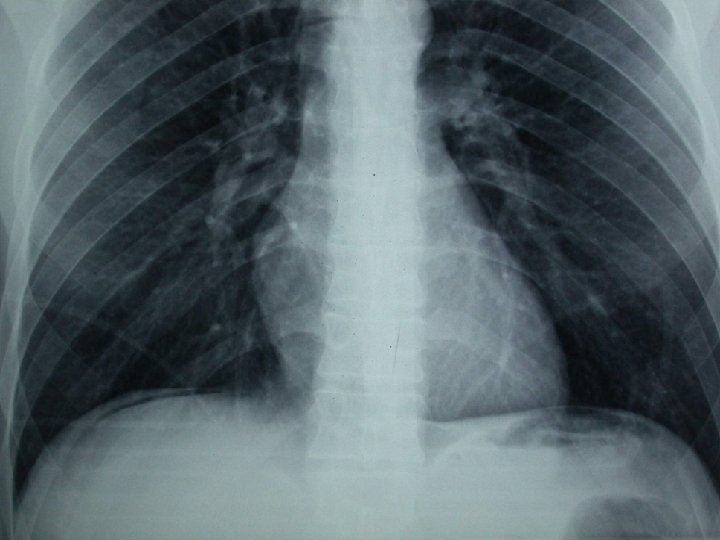

Perforazione di organo cavo: pneumoperitoneo

Pneumoperitoneo